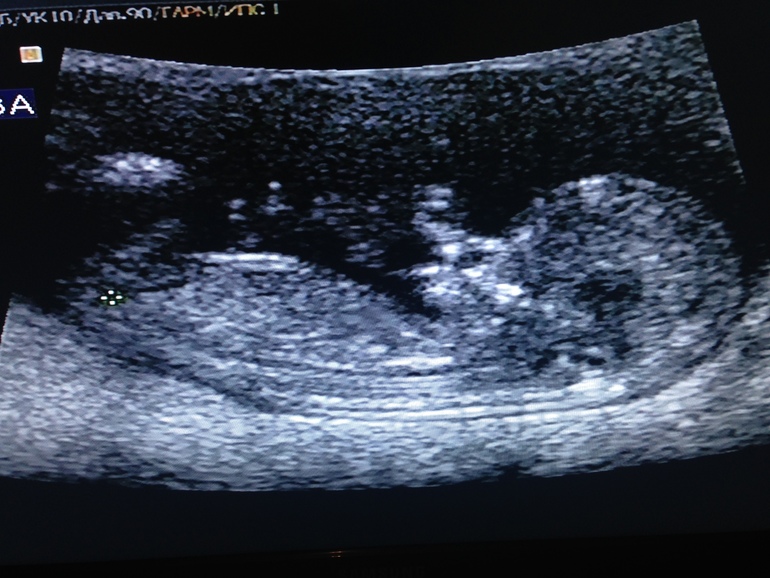

Срок по М 12 и 2 дня

По УЗИ 11 и 6 дней (была поздняя О)

КТР 56

ЧСС 154

Мне в 13 недель такую фотку славную дали...мы там с мужем ротик углядели и улыбочку ))Иногда когда грустно,достаю фоткц и сама улыбаюсь)))у меня тоже поздняя овуляшка и цикл длинный был...тоже в неделю разница

Блин, а мне в 11 неполных недель сделали узи скрининг, там такой маленький человечек. А тут все так отчётливо и голова и тело уже приличных размеров или это увеличенное фото?